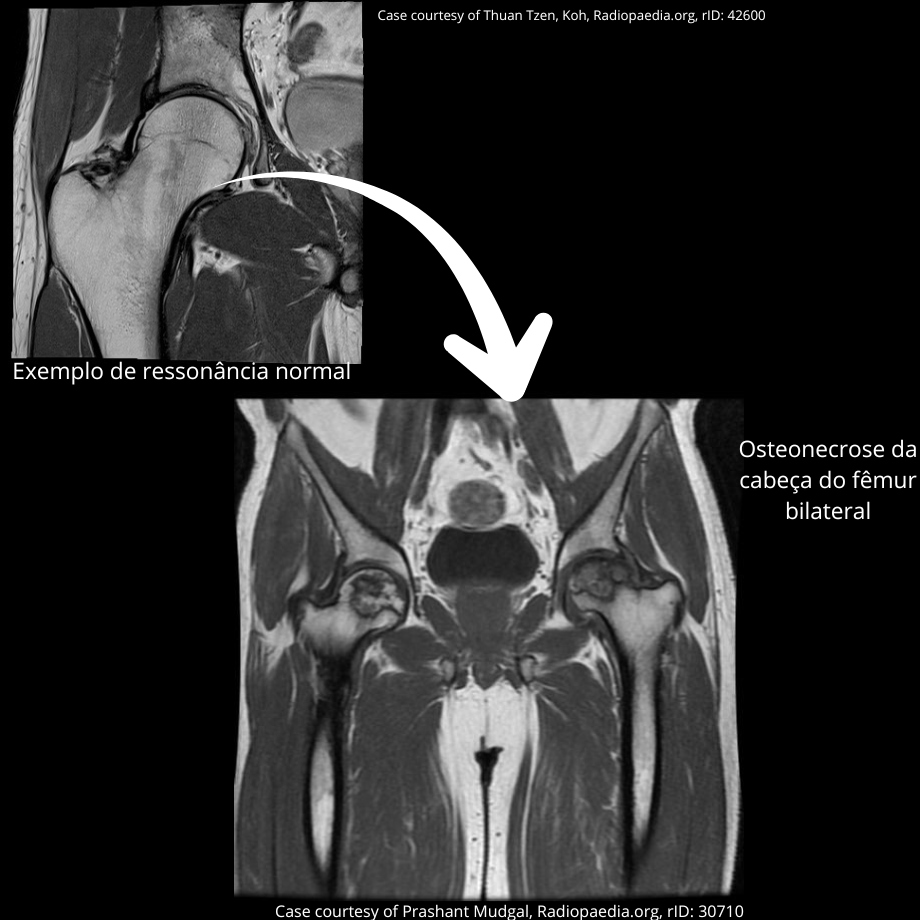

A ressonância magnética do quadril é o exame de escolha e padrão-ouro para o diagnóstico da osteonecrose da cabeça do fêmur. Ela permite detectar a doença precocemente, avaliar a extensão da área acometida e identificar sinais de progressão, como edema da medula óssea, fratura subcondral, perda da esfericidade da cabeça do fêmur e afinamento da cartilagem, que indicam evolução para artrose secundária do quadril.

Outro ponto relevante é o risco de acometimento bilateral. Mesmo quando a dor está presente em apenas um quadril, recomenda-se a avaliação do quadril contralateral com ressonância magnética, especialmente nos casos de osteonecrose secundária